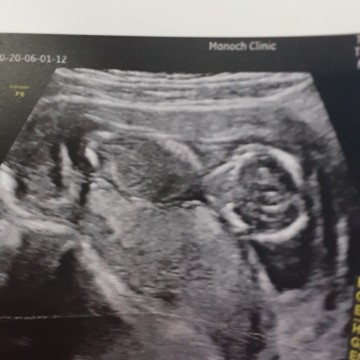

พอจะดูออกไหมคะว่าหญิงหรือชาย

14w+2จ้า หมอบอกยังไม่ชัด

ภาพนี้ไม่สามารถดูเพศได้

ประมาณ19w20w จะเห็นชัดจ้า